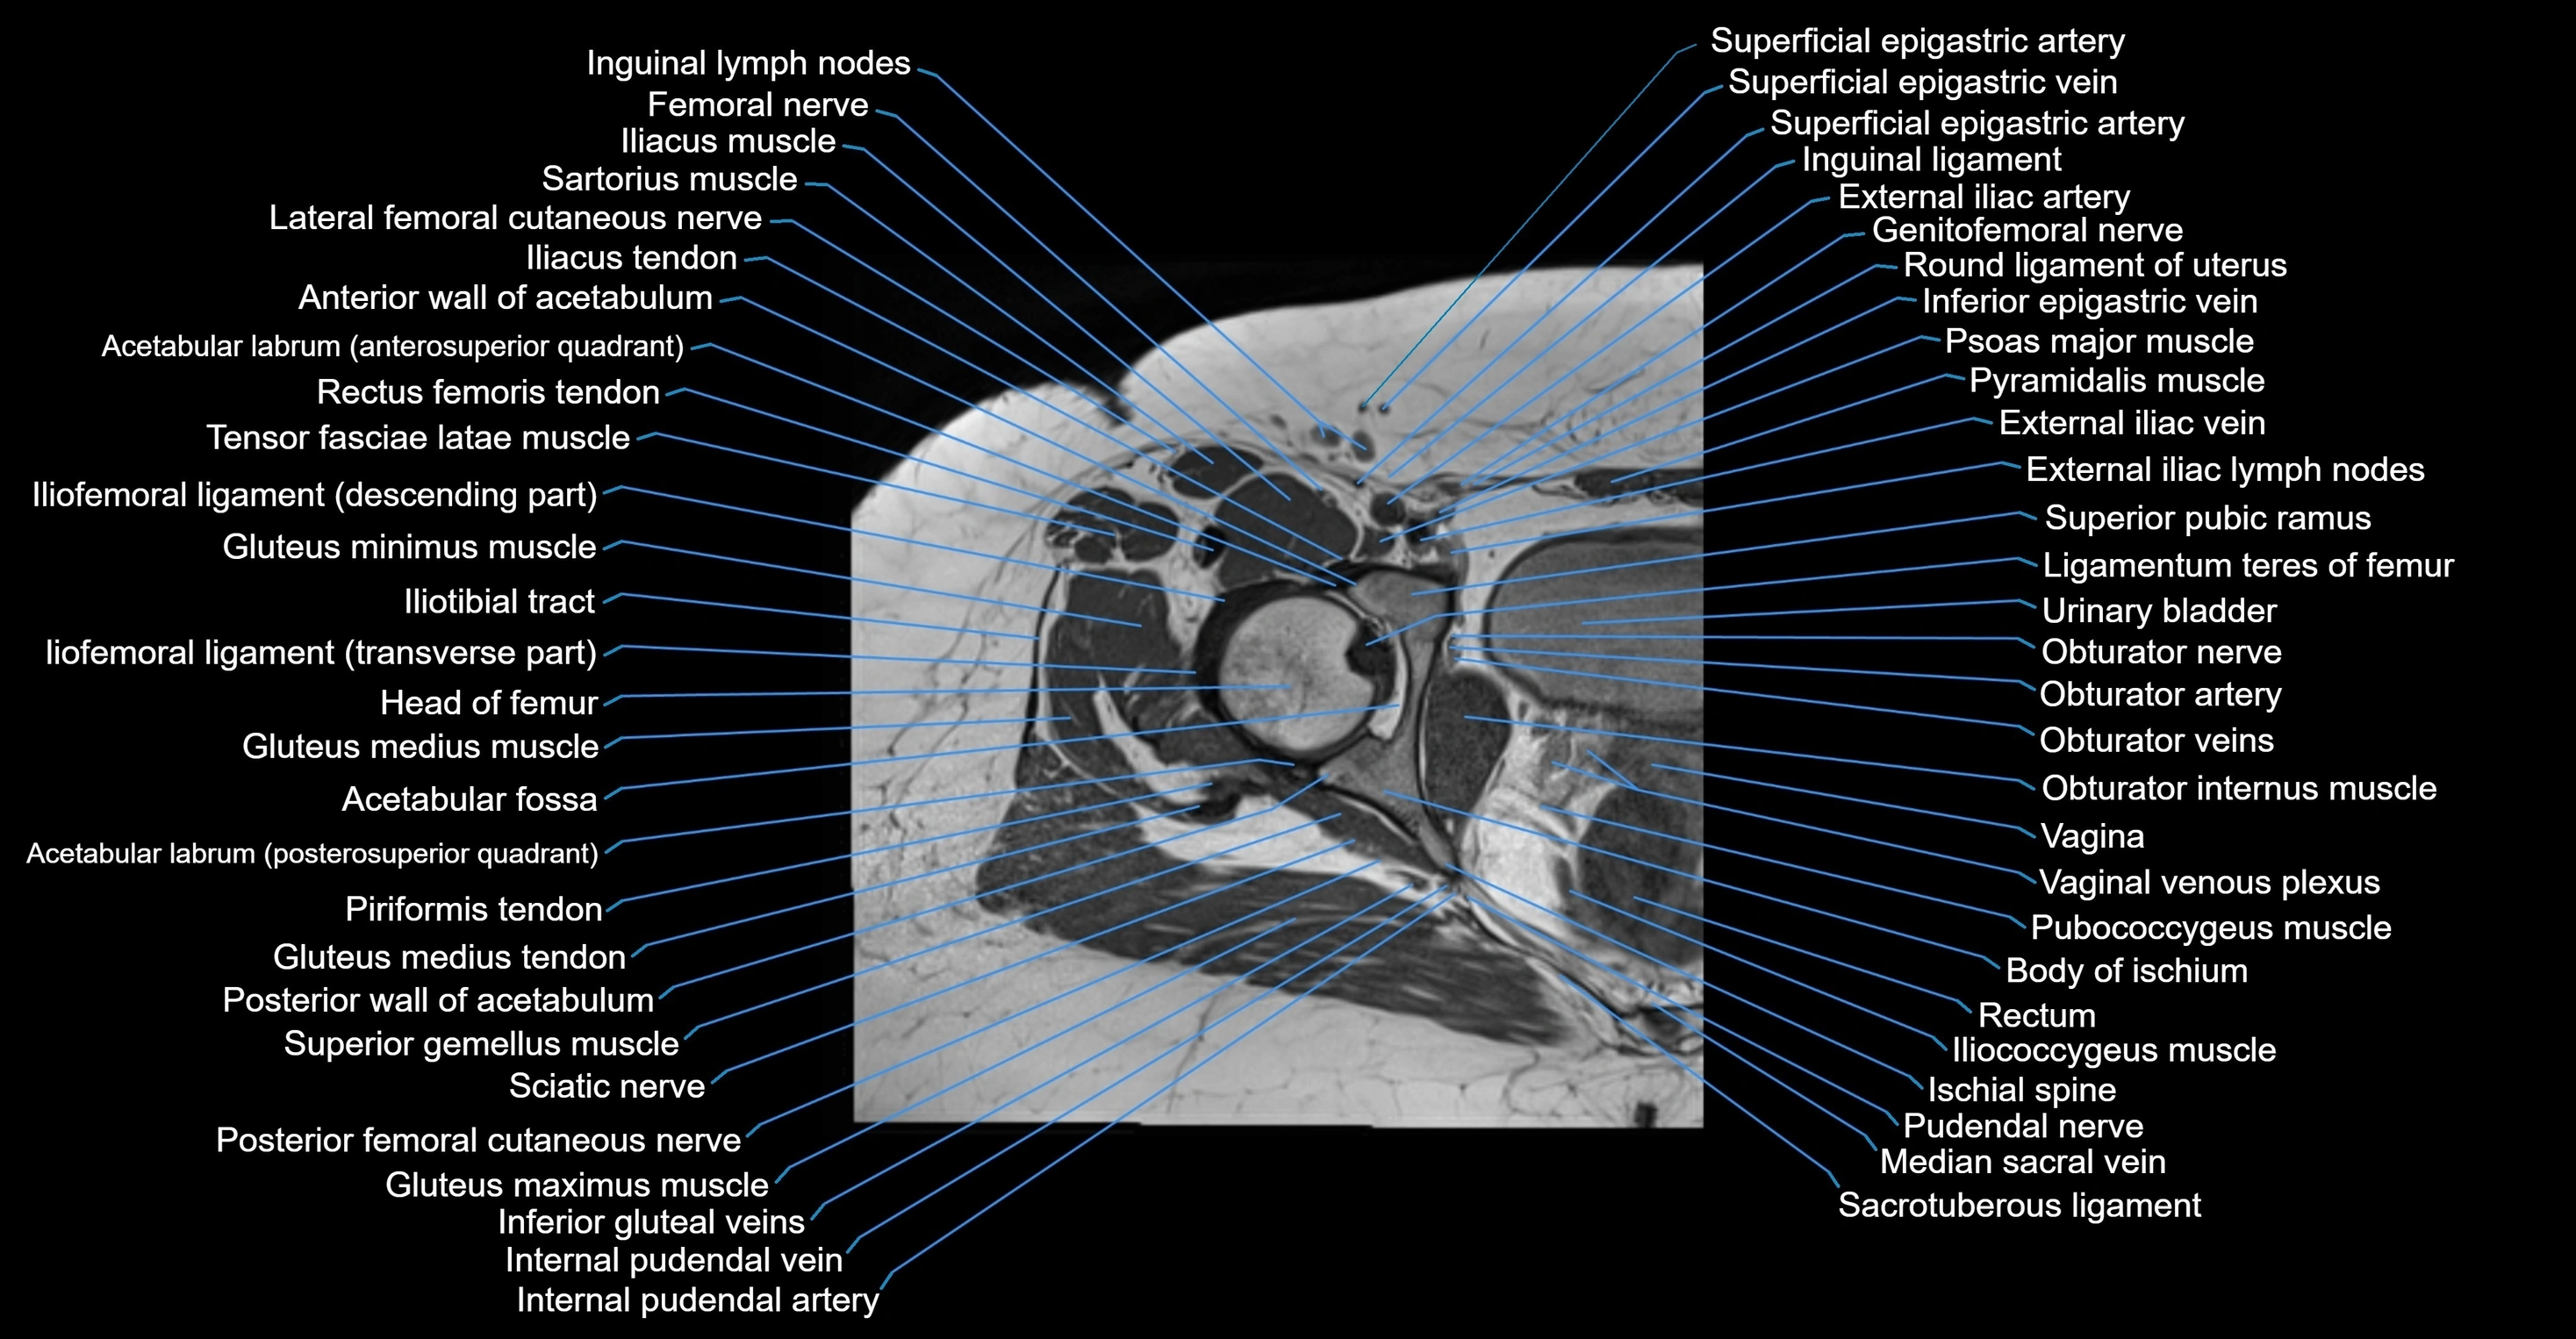

- Acetabular labrum

- Acetabulum

- Anterior wall of acetabulum

- Body of ischium

- External iliac artery

- External iliac vein

- Femoral nerve

- Genitofemoral nerve

- Gluteus maximus muscle

- Gluteus medius muscle

- Gluteus medius tendon

- Gluteus minimus muscle

- Head of femur

- Iliococcygeus muscle

- Iliotibial tract

- Inguinal lymph nodes

- Ischial spine

- Levator ani muscle

- Median sacral vein

- Mesorectal fascia

- Obturator internus muscle

- Obturator internus tendon

- Obturator nerve

- Obturator veins

- Posterior femoral cutaneous nerve

- Pubococcygeus muscle

- Pudendal nerve

- Rectum

- Round ligament of uterus

- Sacrospinous ligament

- Sacrotuberous ligament

- Superior pubic ramus

- Superior rectal vein

- Superior vesical artery

- Urinary bladder

- Uterine venous plexus

- Uterus

- Vagina

- Vaginal venous plexus